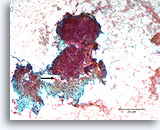

Proliferatieve ductale laesie, Borst FNA, Directe uitstrijk.

Stratificatie van de ductale cellen staat bekend als hyperplasie of proliferatieve veranderingen. Storend bloed en de dikte van de fragmenten maken het moeilijk om in te schatten hoe veel hyperplasie aanwezig is.

Proliferatieve ductale laesie, Borst FNA, Directe uitstrijk.

Stratificatie van de ductale cellen staat bekend als hyperplasie of proliferatieve veranderingen. Storend bloed en de dikte van de fragmenten maken het moeilijk om in te schatten hoe veel hyperplasie aanwezig is.